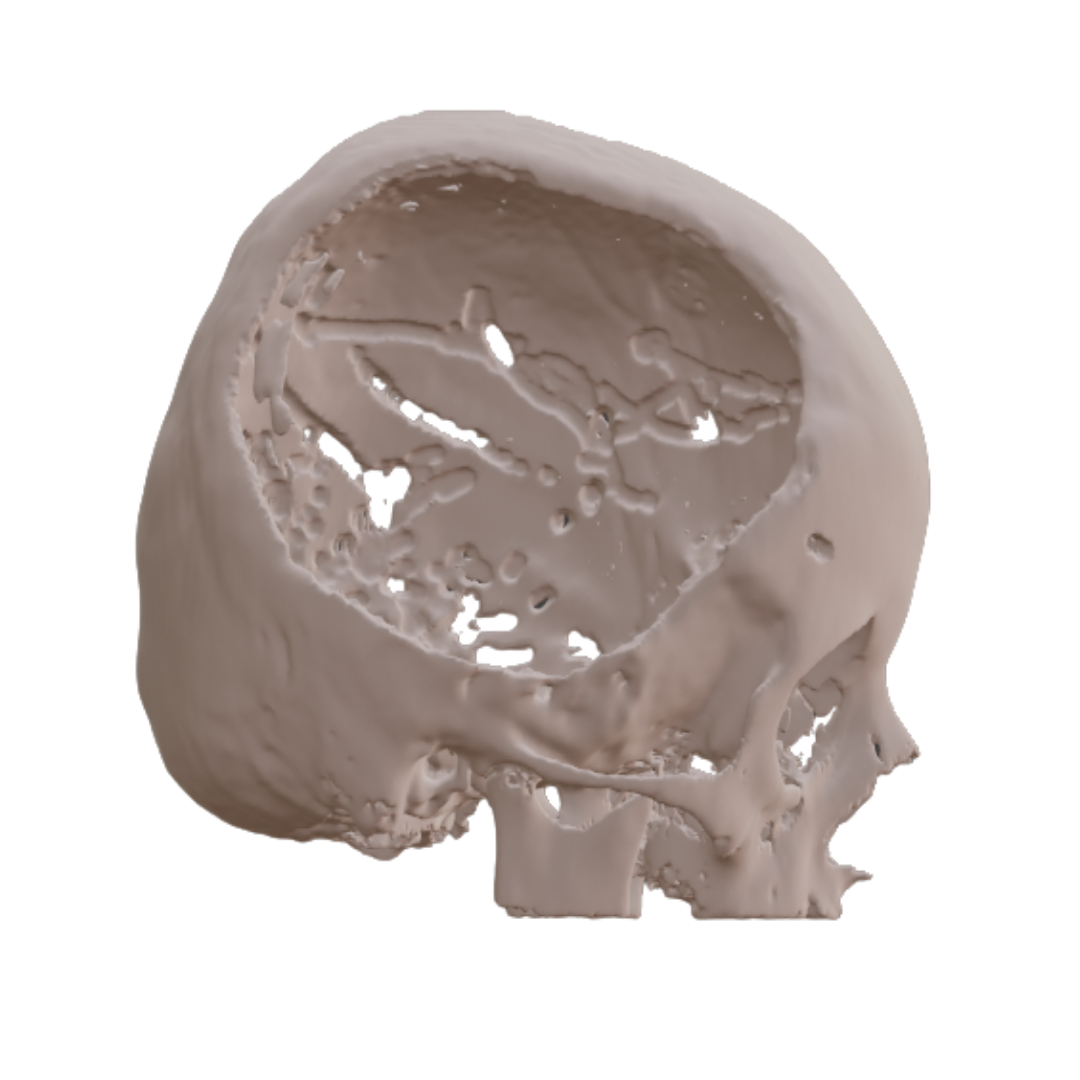

NEURO

Bloocell® is the world’s first “ARTIFICIAL TISSUE TECHNOLOGY” developed in the field of tissue engineering for the treatment of tissue deficiencies. It is a complementary and therapeutic solution that can be manufactured in patient-specific anatomical forms. With its innovative technology, Bloocell® has become the first legal representative of this paradigm worldwide.Clinical results have been consistently successful. Bloocell® is a three-dimensional scaffold designed for the treatment of damaged or missing tissues. It offers a holistic therapeutic approach by supporting cell growth, tissue formation, and the healing process. While reinforcing the tissue structure, Bloocell® also facilitates cell proliferation and differentiation in an optimized environment. Made from biologically compatible materials, Bloocell® does not induce adverse immune responses once integrated into the body. As a bioresorbable scaffold, Bloocell® is gradually absorbed and replaced by new tissue. This process provides an ideal environment for natural tissue regeneration and repair. Bloocell® can reconstruct various tissue types such as bone, cartilage, soft tissue, skin, and nerves. Therefore, Bloocell® offers a broader application range than grafts and carries lower associated risks.